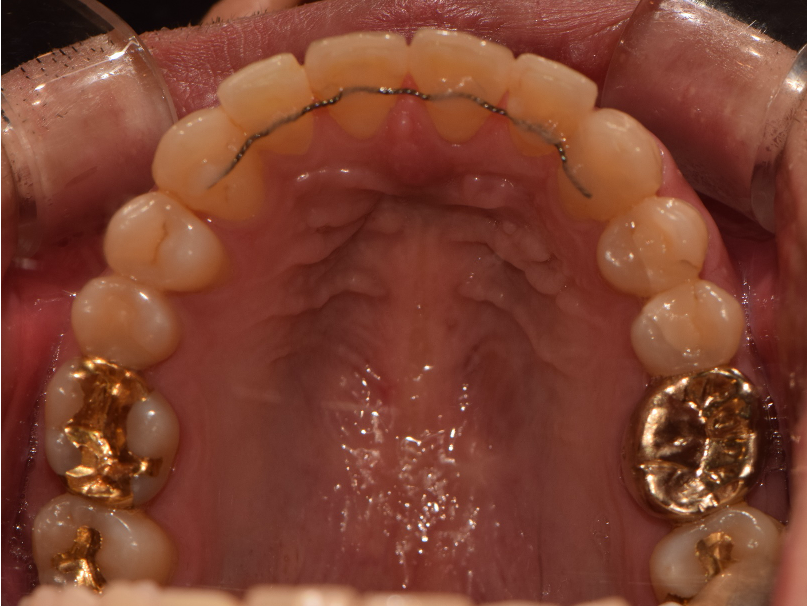

상악 악궁이 좁을 경우에는 하악을 편안하고, 안정적으로 수용하지 못하기 때문에 치아의 배열이 고르지 못하고, 이로 인해 돌출입, 주걱턱과 같은 문제가 생기게 됩니다. 이러한 경우 악궁확장을 통해 미리 증상을 예방하거나 이미 문제가 발생한 경우 시행하여 안정적이고, 바른 치아배열을 만들 수 있습니다. 아래사진은 주걱턱 개선을 위해 양악 수술을 할 줄 알고 큰 근심을 가진 환자를 상악궁 확장을 통한 비수술-비발치 교정으로 치료한 증례입니다.

악궁확장 후 변화